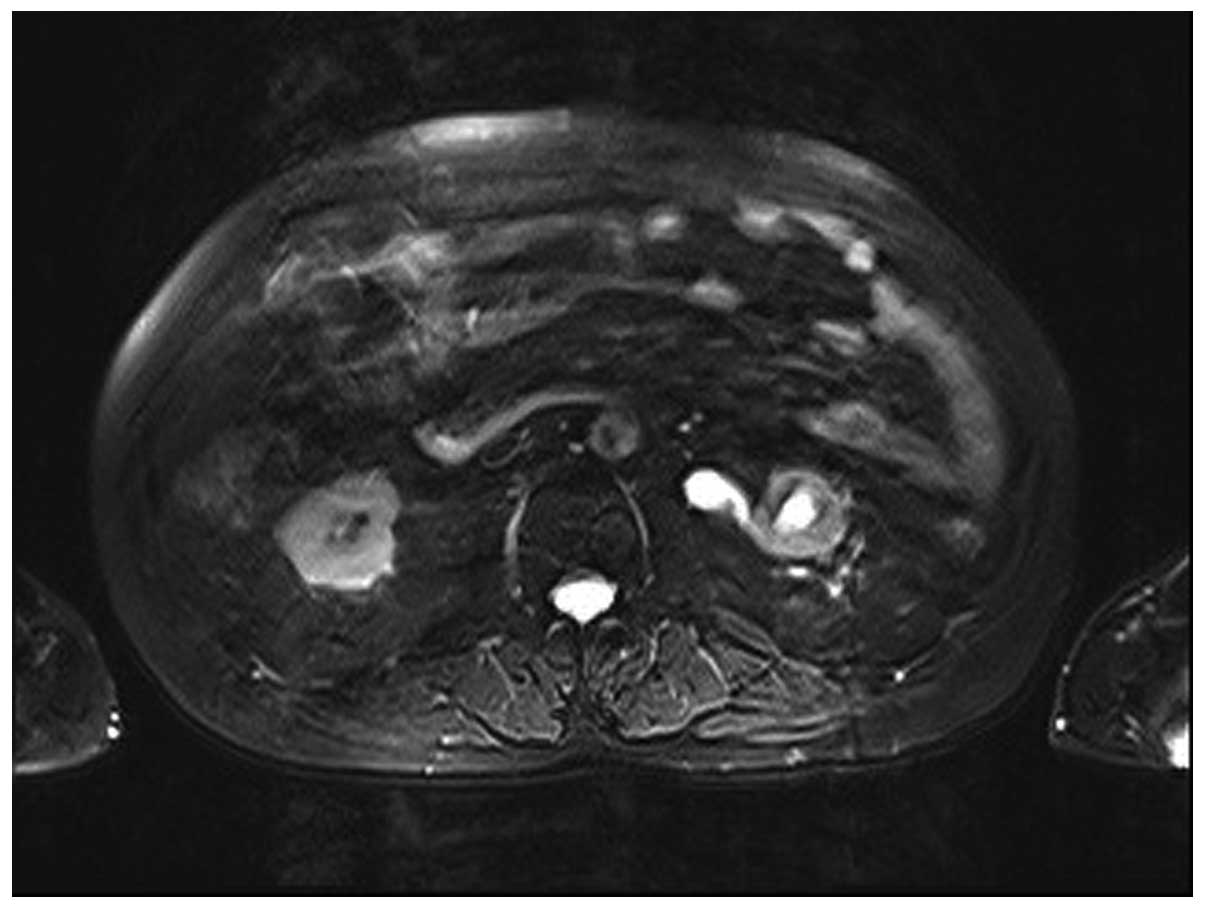

A 69-year-old Chinese Han male patient was admitted to the Department of Urology of Tianjin First Central Hospital (Tianjin, China) with a 10-month history of gross hematuria and 1-month history of left flank pain. The medical history of the patient included 17 years of hypertension, 20 years of coronary heart disease and an allergy to iodine. The findings of the physical examination were normal. The findings of the routine laboratory examinations were unremarkable. However, on urinalysis, there was macroscopic hematuria and 40–50 white blood cells per high-power field. On magnetic resonance imaging of the urinary tract, the iliac wing level around the left ureter exhibited an iso-intense T2 signal, an irregular mass with a rough outline and unclear boundaries of the corresponding level of the left iliac vessels. There was occlusion of the left ureter at the corresponding level, with hydronephroureterosis above the mass and undevelopment of the segment of the left ureter below the mass (Figs. 1, 2 and 3). The right kidney was normal. Chest radiographs were performed and revealed no primary or metastatic lung lesions. Left nephroureterectomy was performed and the clinical diagnosis was primary ureteral tumor. The gross examination revealed an ovoid, solid, white mass, sized 3.5×3.0×1.6 cm, originating from the ureteral mucosa and protruding into the ureteral lumen, with invasion of the periureteral adipose tissue. Examination under a light microscope revealed that the tumor was composed of atypical carcinoid cells with diverse shapes, with common mitotic figures, and small cells with a round to fusiform shape, scant cytoplasm, fine granular nuclear chromatin, and absent or inconspicuous nucleoli (Fig. 4). The tumor cells exhibited cytoplasmic positivity for cytokeratin (CK)7, epithelial membrane antigen (EMA), CD56 and synaptophysin, and negativity for neuron-specific enolase (NSE), chromogranin A (CgA) and CK20. The Ki-67/MIB1 index was 20%. The patient was diagnosed with NEC of the ureter with atypical carcinoid and small-cell carcinoma components. The postoperative recovery of the patient was uncomplicated; however the patient refused chemotherapy or radiotherapy. During the regular follow-up examinations, there was no evidence of tumor recurrence at 5 months postoperatively; however, he succumbed to extensive metastases after 12 months of follow-up.

Figure 1.

Occlusion of the left ureter, with hydronephroureterosis above the mass.